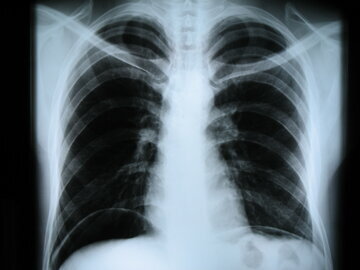

Согласно последним исследованиям ученых, гипертония у женщин имеет свои особенности. Есть такие формы, которые в принципе невозможны у мужчин: например, в виду гипертонию беременных и климактерического периода. Также гипертония — это чаще всего женская проблема. Две трети страдающих этим недугом — представительницы прекрасного пола

У женщин заболевание протекает значительно тяжелее. Выше показатели артериального давления, чаще появляются болезненные ощущения. У них гипертония нередко сосуществует вместе с другими недугами, создавая целый букет заболеваний. Там могут быть и диабет, и ожирение, и варикозное расширение вен, и нарушения липидного обмена. Все это затрудняет эффективность лечения. В последнее время жизнь женщины и ее положение в обществе очень изменились. На ее плечи легли те обязанности, которые для нее не характерны. Отсюда напряжение, перегрузки, стресс. А это отнюдь не улучшает здоровье и не понижает давление.